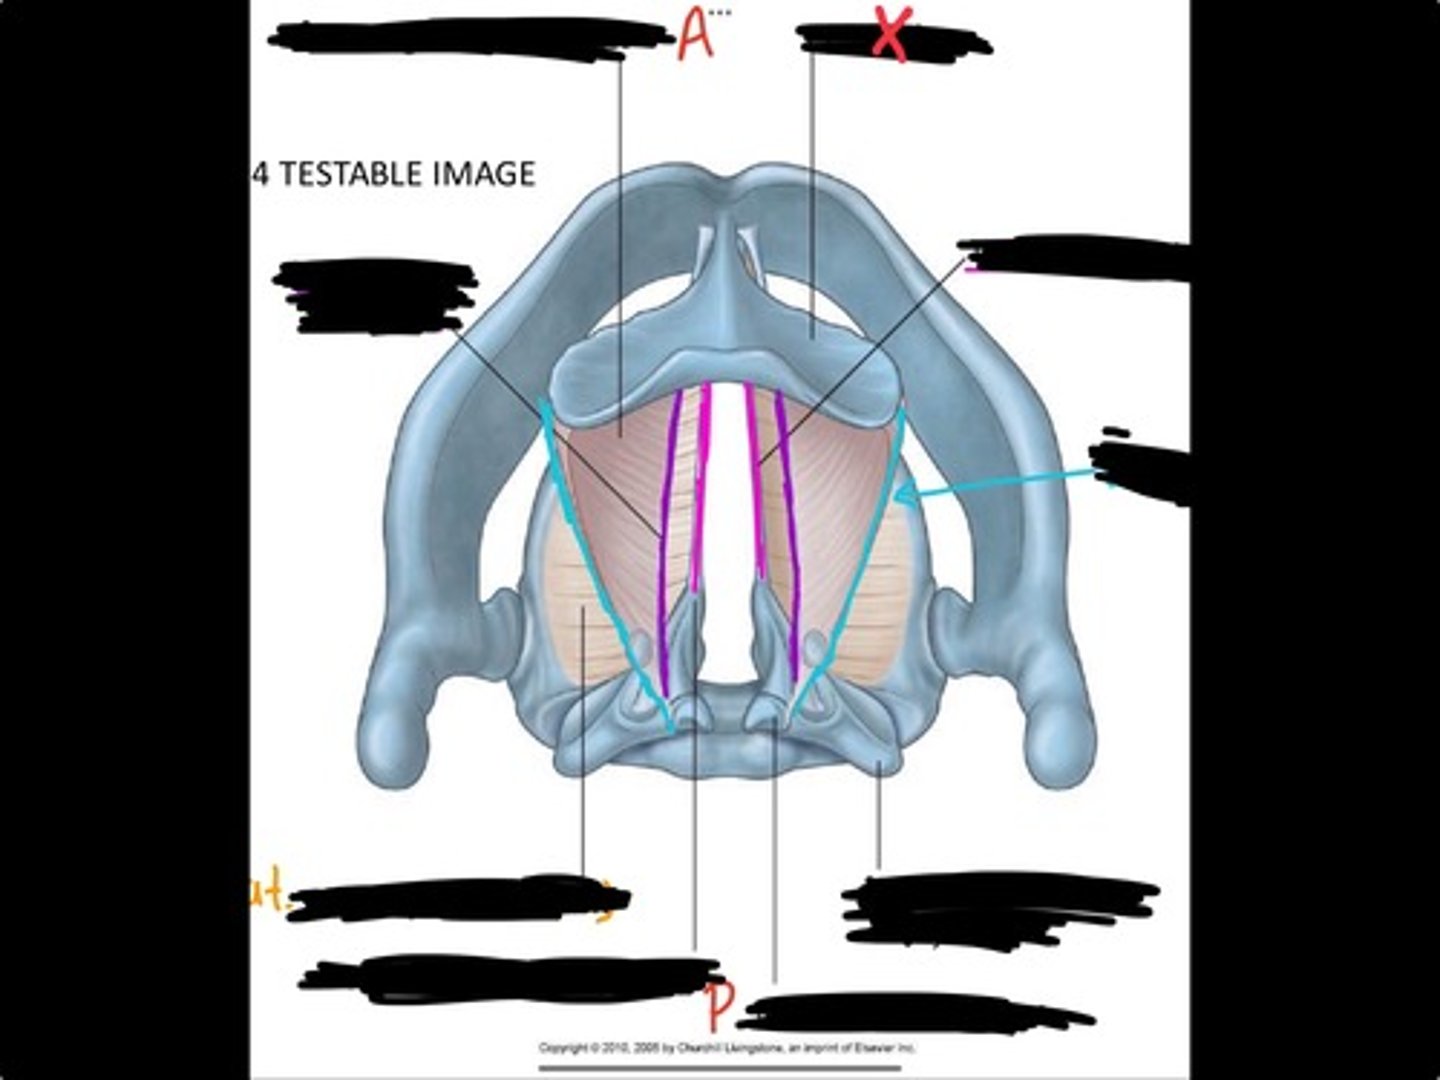

Vocal process of arytenoid

Conus elasticus

Vestibular ligament

Quadrangular membrane

Epiglottis

vocal ligament

Aryepiglottic ligament

Muscular process of arytenoid

Corniculate cartilage

Posterior crico arytenoid

oblique arytenoid

transverse artyenoid

Rima glottidis

Vocal ligament

Vocalis muscle

Lateral cricothyroid ligament

Lateral cricoartenoid